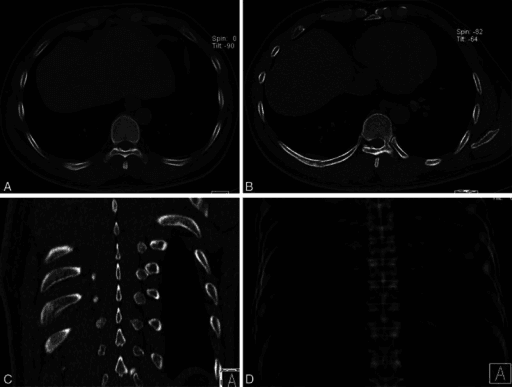

Clinical Imaging

Imaging Gallery

Window and Level Settings

A CT image dataset contains a far wider range of HU values than a monitor can display (typically 256 grey levels). Window width determines the range of HU values displayed, and window level (centre) determines the midpoint of this range.

Standard CT Window Settings for Orthopaedic Imaging

| Window | Width (HU) | Level (HU) | What It Shows |

|---|---|---|---|

| Bone window | 2000-4000 | +300 to +500 | Cortical detail, fracture lines, implant position, calcification |

| Soft tissue window | 250-400 | +40 to +60 | Muscle, haematoma, soft tissue masses, fluid collections |

| Lung window | 1500-2000 | -600 | Air-containing structures, pneumothorax |

| Brain window | 80-100 | +35 to +40 | Intracranial pathology (relevant for polytrauma assessment) |

The critical concept for the examination is that changing window settings does NOT change the data — it simply changes which portion of the Hounsfield scale is displayed on screen. The same dataset can be viewed on bone windows (to assess fractures) and soft tissue windows (to assess haematomas) without rescanning the patient.